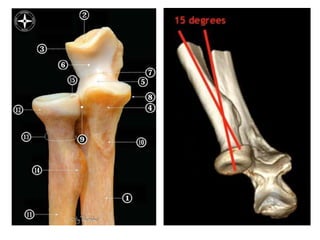

Flexion/Extension

• Dominant=non-dominant

- Age, sex, muscularity

• Anterior offset of distal humerus

• Uniaxial hinge

• Carrying angle 11-14deg

• Axis: abducted by 50% of CA

Pronation/Supination

• 80deg pronation

• 90degree supination

• Axis: radial head to ulnar head

• RH: Proximal migration of radius

with pronation